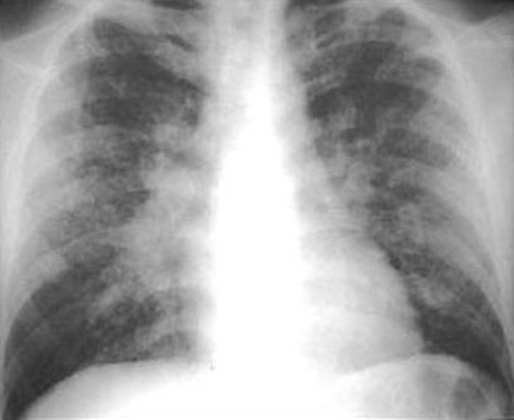

Sarcoidosis Type II

Type II: Adenopathy with parenchymal infiltrates